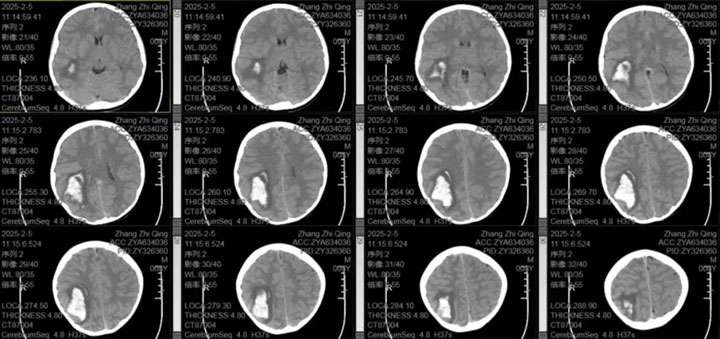

据了解,该患儿系上海人,春节期间随父母从上海返乡过节,最初出现头疼症状,家人未予以足够重视。随后,患儿病情加重,出现呕吐及视物模糊的情况,家人紧急将其送往东方总院。经头颅CT检查显示患儿右侧颞顶枕叶脑出血。

神经外科医疗中心吴鹏副院长解释道:小儿脑出血在临床上较为复杂,常见原因包括脑血管畸形、动脉瘤、血液系统疾病等,其中脑血管畸形最常见,处理较为复杂,手术风险极高。为进一步明确病因,排除脑血管畸形、动脉瘤等可能,立即为患儿进行了头颅CTA检查,结果未发现明显异常。